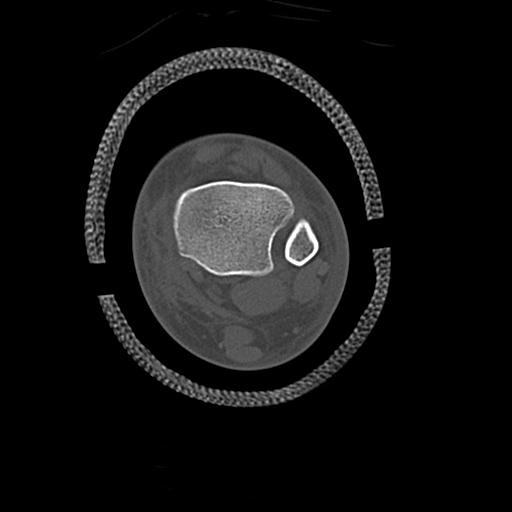

102755 1/4 2R 1/15 2R 右足関節 68歳女性 右三果脱臼骨折